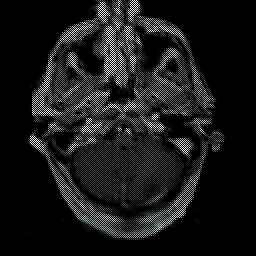

Glioma Overlay -- Slice #3

[Home][Help][Clinical] Slice 3